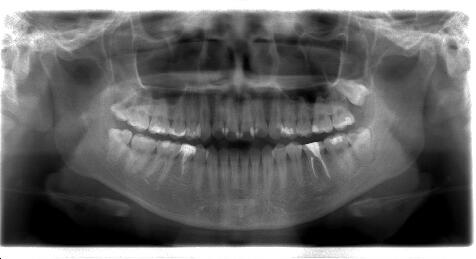

(2)初見では抜歯もしくは遠心根を抜去(ヘミセクション)を考慮しましたが、20代前半で

まだ若いため、約1年半をかけて根の治療を行いました。 ![]() ![]() ![]()

パノラマ画像:黒く写っている病巣が徐々に小さくなっていく様子が分かります。

![]() ![]()

CT画像:当初病巣の下底は下顎管付近まで、また頬側の皮質骨にも穴が開いています

が、徐々に黒い病巣部分が小さくなってきている様子が分かります。 2.再植を応用した根の治療